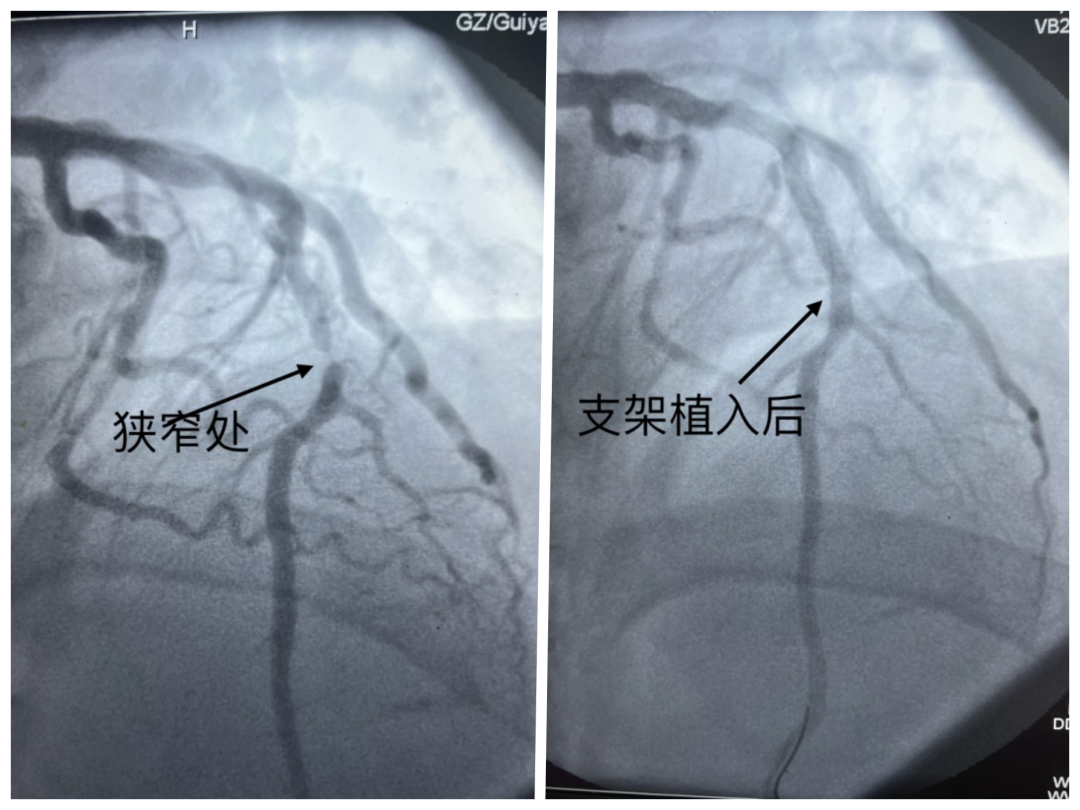

2024年5月23日,来自贵州52岁的李先生出现牙痛并伴随不明显的胸痛,他以为是牙病犯了,便自行服用“甲硝唑”等消炎止痛药,但未见好转。不料四天后的凌晨,李先生的牙痛和胸痛突然加剧,全身冒汗,遂就医。

医生为其进行心电图检查,结果提示急性广泛前壁心肌梗死。随后,医生在其狭窄血管处植入支架,李先生转危为安。